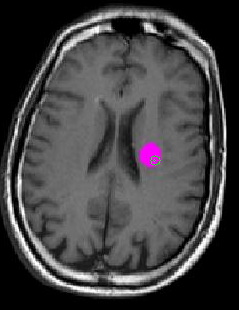

Perpendicular Annotation

This annotation type is used when alpha is between 60 and 90 degrees.

A circle and a dot appear on the screen, as follows:

• The circle appears where the needle will enter the slice.

• The dot appears where the needle will exit the slice.

An example of this kind of annotation is shown in figure 2.

Fig. 2 | Perpendicular Annotation.